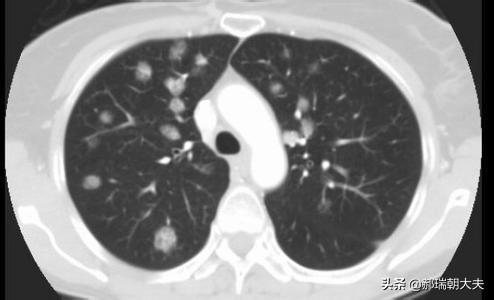

Les examens médicaux étant de plus en plus fréquents, les nodules pulmonaires sont de plus en plus souvent détectés. Les nodules pulmonaires sont un terme d'imagerie, et la définition d'imagerie d'un nodule pulmonaire est une petite lésion bien définie qui est complètement entourée par le parenchyme pulmonaire (Diamètre ≤30mm). La morphologie des nodules est classée comme solide ou sub-solide ; les nodules sub-solides sont eux-mêmes classés en nodules de verre dépoli et en nodules partiellement solides. Les lésions de plus de 30 mm de diamètre sont des masses plutôt que des nodules et ont une probabilité plus élevée d'être malignes.

La définition actuellement acceptée d'un nodule pulmonaire est une ombre pulmonaire focale, arrondie, hyperdense, solide ou subsolide, d'un diamètre ≤3 cm. Ces dernières années, avec l'augmentation de la population examinée par tomodensitométrie à faible dose, la proportion de nodules pulmonaires multiples détectés en plus des nodules pulmonaires isolés a considérablement augmenté. Les nodules pulmonaires multiples se présentent souvent sous la forme d'un nodule pulmonaire unique accompagné d'un ou plusieurs petits nodules. Les nodules pulmonaires multiples sont définis comme 2 lésions ou plus. Les patients présentant des nodules pulmonaires multiples peuvent avoir plusieurs sources de cancer du poumon précoce ou de lésions précancéreuses confirmées chirurgicalement et nécessitant une attention clinique particulière.

Nodules pulmonaires : Il s'agit de lésions qui apparaissent dans les tissus des poumons. Il s'agit de lésions arrondies ou irrégulières d'un diamètre inférieur ou égal à 30 mm, souvent entourées de tissu pulmonaire normal. Sur l'imagerie médicale, ils sont décrits comme des "ombres hyperdenses dans les poumons". Les nodules pulmonaires peuvent être uniques ou multiples, avec des limites claires ou floues.

En fonction de l'uniformité de la densité des nodules, on peut les classer en nodules substantiels, en nodules de verre dépoli purs et en nodules de verre dépoli mixtes.